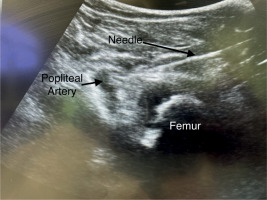

iPACK block procedure (Figure 1)

After the spinal anesthesia and before the surgical incision, the iPACK block was performed. The patient was placed in the supine position. We used a linear, high-frequency 4–8 MHz sono-graphic ultrasound probe and a 22-gauge needle (Stimuplex Ultra 360, 80 mm, Melsungen, Germany). The transducer was placed transversely over the medial aspect of the knee, 2–3 cm above the patella. The transducer was slid proximally to identify the distal femoral shaft and popliteal artery. The needle was inserted in-plane, from the anteromedial facet of the knee, into the space between the femur and popliteal artery. When the posterior part of the popliteal artery was reached, hydro-location positioning was performed with 2 mL of 0.9% isotonic saline. After the negative aspiration, 20 mL of 0.2% ropivacaine was placed between the posterior knee capsule and the popliteal artery.